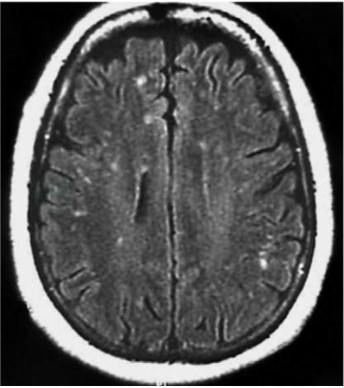

脑CT多无异常。MRI检查可见大脑半球深部脑室周围白质散在的大小不等斑片状异常信号灶,T1WI呈均匀低信号,T2WI为明显高信号,无明显占位效应,少数病例脑干、小脑有异常信号,受累脊髓节段变细(Morgan,2007)(图1)。脊髓MRI出现T2WI高信号,提示HAM/TSP为快速进展期,临床表现为严重的运动功能受累(Yukitake,2008)(图2),MRI检查正常并不能除外HAM/TSP。

图1HAM/TSP患者脑 MRI检查,在 Flair像可见大脑局灶高信号病变

引自:神经病学:全2册.第3版.ISBN:978-7-117-31406-0.主编: